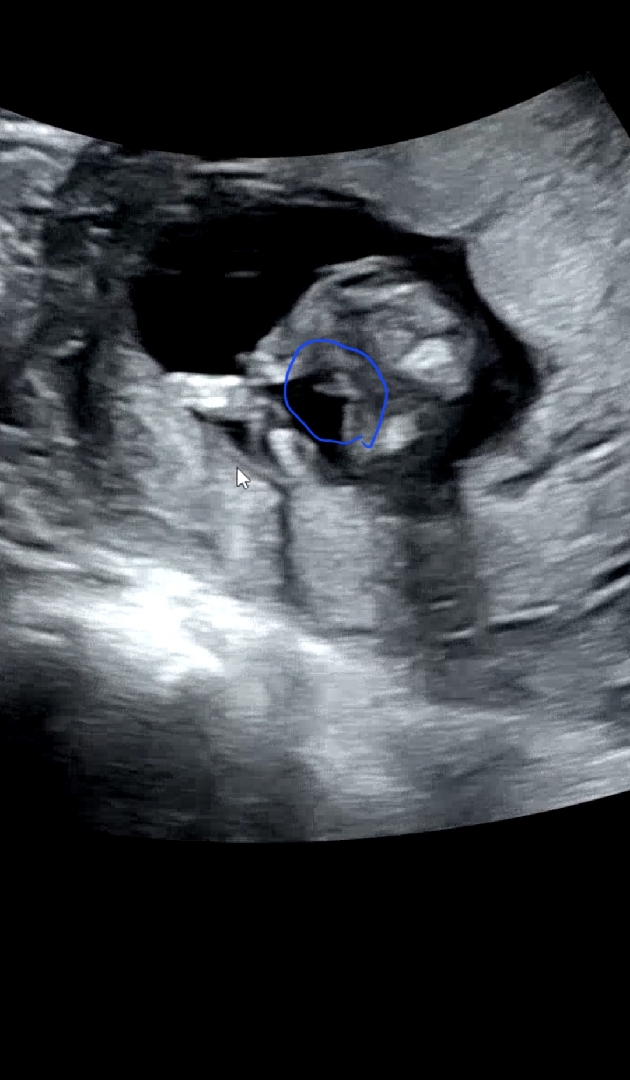

14주0일차 초음파사진 이거 🌶 일까요?

엉덩이밑에 다리사이 길쭉한 먼가있는데 멀까요?ㅜ